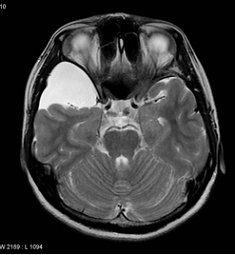

Doktorunuz semptom ve bulguları değerlendirdiğinde hidrosefaliden şüphelenirse tanıyı koymadan önce ayrıntılı bir şekilde hastalığın gidişatını öğrenmeli, ayrıntılı bir fiziksel ve nörolojik inceleme yapmalı, CT veya MRG ile görüntüleme yapmalıdır. Tetkikler sonucunda hidrosefali teşhisi konursa hasta daha ileri tetkik ve tedavi için beyin cerrahi uzmanına refere edilmeli.